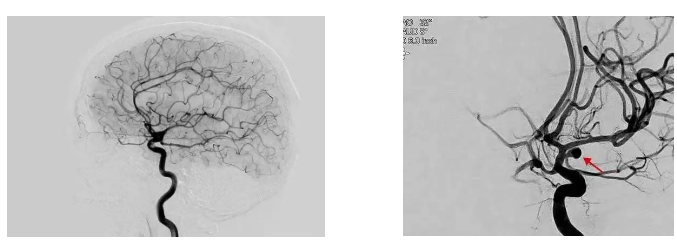

脑血管造影(DSA)是检查脑血管最准确的方法,被称为诊断脑血管病的“金标准”。

简单说:把造影剂打到血管里,通过X光动态看清脑血管有没有狭窄、堵塞、动脉瘤、畸形、出血等问题。